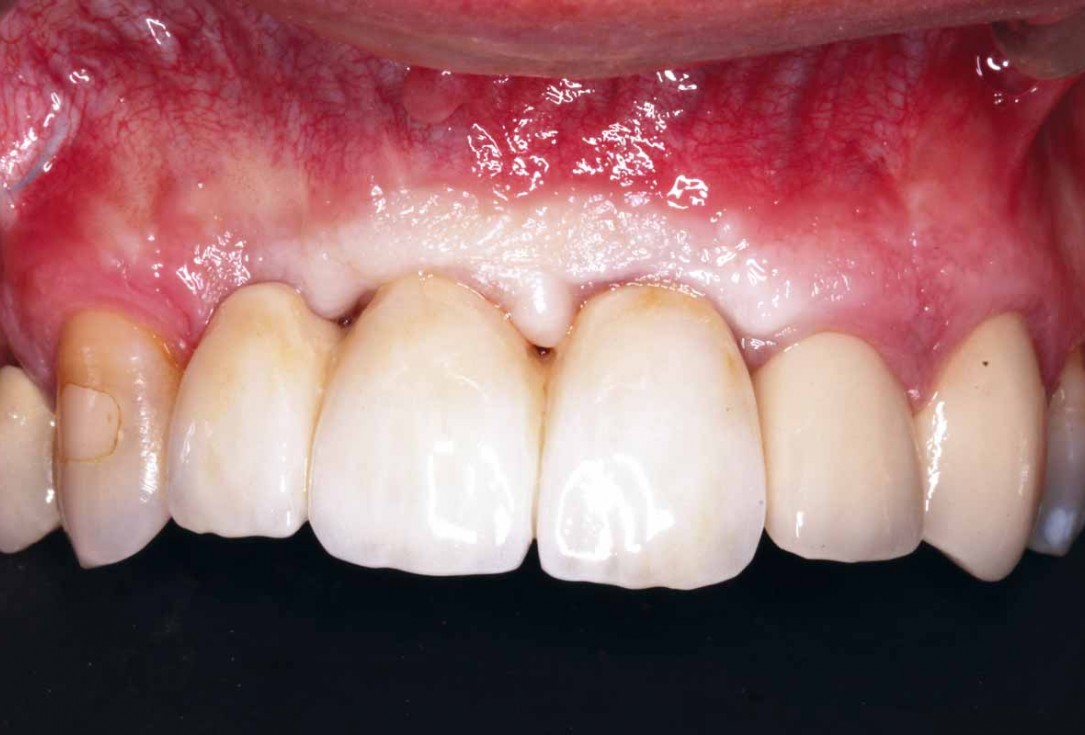

24/27 - 18 weeks after surgery with visible soft tissue maturation and papilla growing back

GBR and soft tissue augmentation with cerabone® and mucoderm® - H. Maghaireh & V. Ivancheva